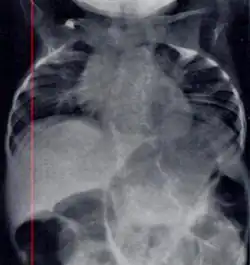

Radiograph depicting typical skeletal features of Jarcho-Levin syndrome, subtype spondylothoracic dysplasia. Note fanlike configuration of the ribs, with extensive posterior fusion, along with multiple vertebral segmentation defects.

Spondylothoracic dysplasia, or STD, has been repeatedly described as an autosomal recessively inherited condition that results in a characteristic fan-like configuration of the ribs with minimal intrinsic rib anomalies. Infants born with this condition typically died early in life due to recurrent respiratory infections and pneumonia due to their restricted thorax.[3][4][5] Recently, a report[6] has documented that actual mortality associated with STD is only about 50%, with many survivors leading healthy, independent lives.